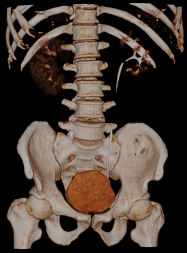

Chẩn đoán hình ảnh mô mềm tiên tiến cho vùng bụng.

Tăng cường độ tương phản I-ốt.

Hỗ trợ đánh giá an toàn cho bệnh nhân.

Đảm bảo hình ảnh chất lượng cao.